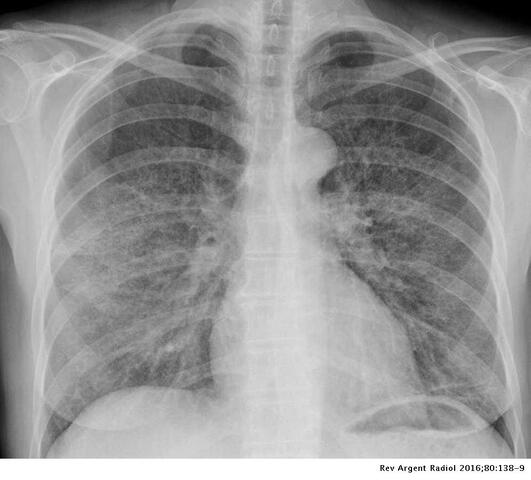

El 5 de junio de 1981, la organización estadounidense de vigilancia y prevención de enfermedades (CDC) informó sobre una forma rara de neumonía entre jóvenes homosexuales de California. Se trata de la primera alerta sobre el SIDA, aunque en ese momento la enfermedad carecía de nombre.